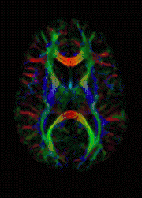

The imaging of this property is an extension of diffusion MRI. If a series of diffusion gradients (i.e. magnetic field variations in the MRI magnet) are applied that can determine at least 3 directional vectors (use of 6 different gradients is the minimum and additional gradients improve the accuracy for "off-diagonal" information), it is possible to calculate, for each voxel, a tensor (i.e. a symmetric positive definite 3×3 matrix) that describes the 3-dimensional shape of diffusion. The fiber direction is indicated by the tensor's main eigenvector. This vector can be color-coded, yielding a cartography of the tracts' position and direction (red for left-right, blue for superior-inferior, and green for anterior-posterior).[45] The brightness is weighted by the fractional anisotropy which is a scalar measure of the degree of anisotropy in a given voxel. Mean diffusivity (MD) or trace is a scalar measure of the total diffusion within a voxel. These measures are commonly used clinically to localize white matter lesions that do not show up on other forms of clinical MRI.[46]